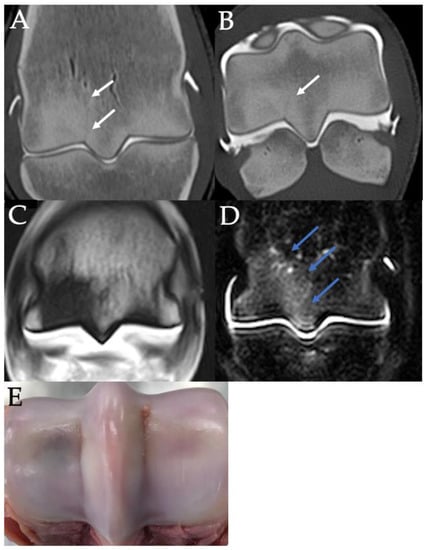

3.4. PSG Subchondral Bone Defects

3.5. PSG Cartilage Defects

3.6. PSG STIR Hyperintensity